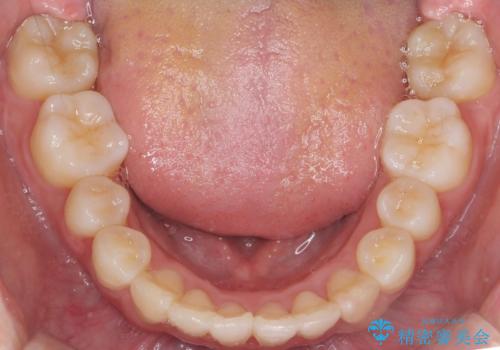

前歯は重度のがたつき、また奥歯はすれ違っていました。

治療は3年以上かかりそうと説明しましたが、2年台で終わらせることができました。

上下左右4本抜歯の可能性を説明していましたが、実際は上顎2本の小臼歯抜歯で済みました。

矯正用インプラントを使用して治療しています。

上下の顎の幅もあっておらず、成人でしたが手術なしで上あごを骨から広げる処置(急速拡大装置)を行いました。